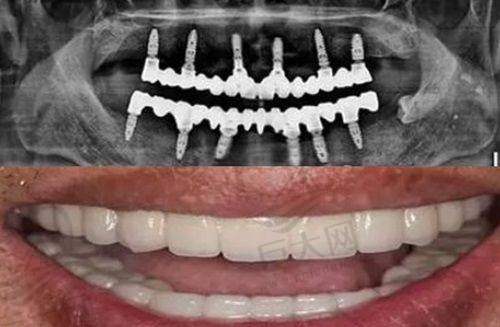

本溪珂媄口腔专长项目包括隐形矫正、牙齿种植、补牙等。可解决龅牙、牙齿稀疏、开颌、深覆合等牙齿畸形情况,能进行韩国种植体种植、美国/瑞士等地的进口种植牙种植,解决牙齿缺失问题,补牙、洗牙等小项目也特别出色。其特色补牙材料珂媄3M纳米树脂,提高耐磨性和强度,有更好的抛光和保持性,多号色仿真设计使补牙更逼真。